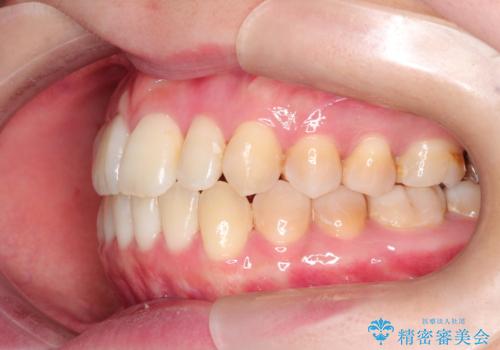

- 前歯のガタガタと、かみ合わせを改善したいとのことで来院されました。

人前でお話をするお仕事のため、装置をつけないでよいマウスピース矯正を希望されました。

下顎の歯が、上顎の歯に対して前方に位置していたので、下顎の歯を後方に移動させるのと、歯と歯の間を削りスペースを作り、歯を並べる計画としました。

お仕事の関係で使用時間が制限されるときもあり、治療期間が予想より少し長くなりましたが、装置をつけずに治療を終えることができました。